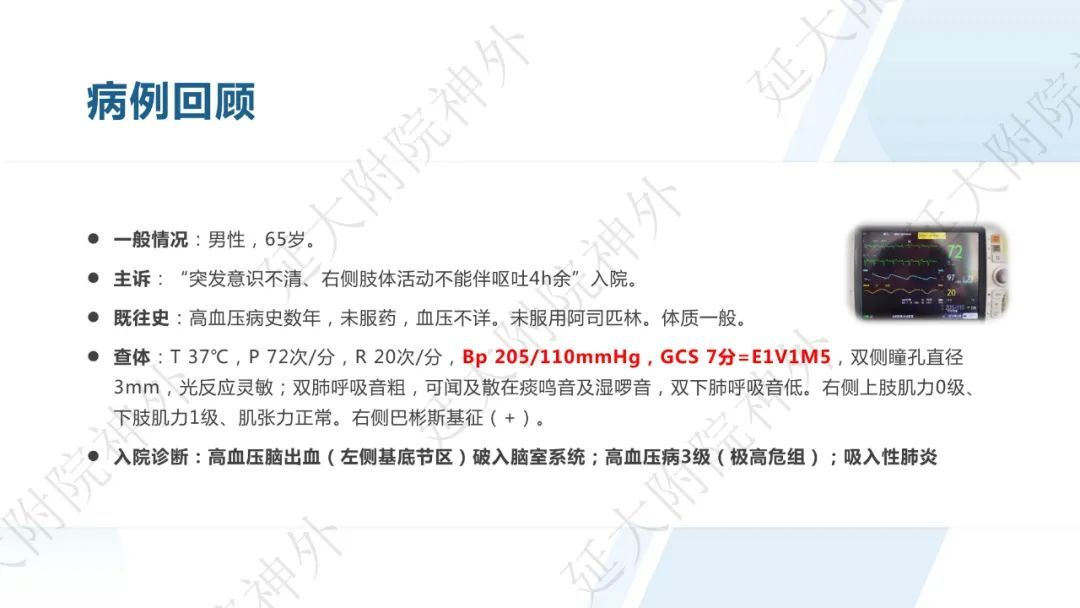

今天为大家分享的是《监测有道丨颅脑创伤-神经重症周刊》第332期,由延安大学附属医院神经外科贾云峰主任医师带来的:左侧基底节区出血破入脑室一例神经内镜下血肿清除术,欢迎阅读、分享。